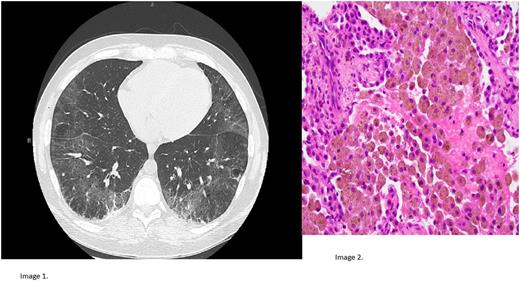

He had a similar presentation 8 months prior, in October 2016. CT chest was remarkable for ground-glass opacities, pulmonary fibrosis, emphysema, and mild bilateral hilar adenopathy. There was nephrotic range proteinuria, and albumin was 1.9. He was given ferric gluconate with improvement in his symptoms, and was discharged four days later with HGB of 9.2. He was lost to follow up until May, and did not receive scheduled EBUS and lung biopsy. Repeat CT scan was performed on second admission, showing interval progression of peripheral fibrosis and honeycombing (Image 1).

Investigations in 2017 included an EGD/colonoscopy, with single duodenal biopsy finding of increased intraepithelial lymphocytes, with preserved villous architecture, h. pylori negative. Tissue transglutaminase IgA was >250 U/mL and anti-gliadin IgA was 26 U/mL. Genetic testing revealed HLA DQ2 serotype. There was no evidence of CHF or pulmonary HTN on Echo. Hemoglobin electrophoresis revealed no abnormal hemoglobin migration and physiologic HbA2 and HbF levels. B12 and folate levels were within normal limits. Lung biopsy revealed alveolar filling with numerous hemosiderin laden macrophages, in background of alveolar pneumoconiosis and phlebosclerosis, (image 2, high magnification).